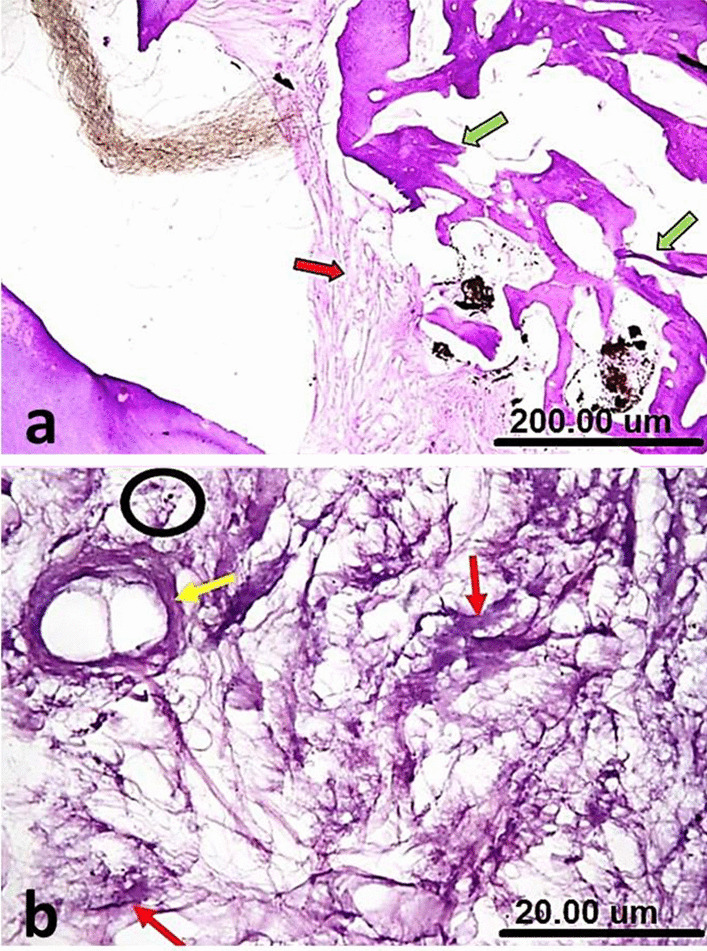

The samples of group I (NeoMTA plus®) showed bridging of the furcation defect by prominent calcific tissue overlying areas of heavily deposited collagen bundles in different directions. There was a condensation of fibrous tissue into a hyaline matrix of hard tissue formation with very scanty inflammatory cells. The interradicular bone trabeculae had normal histologic morphology, regarding thickness, outline, and cellularity/vascularization (Fig. 2a). Diffuse patchy calcification was also seen at the furcation defect, along the dense collagen fibers and around the blood vessels (Fig. 2b).

Fig. 2.

(a) A sample of group I (NeoMTA Plus®) after one week showing bridging of the furcation defect by prominent calcific tissue (thin black arrows) that overlying areas of heavily deposited collagen bundles (green arrow), onset of condensation of fibrous tissue into a hyaline matrix of hard tissue formation (blue arrow) and normal histologic morphology (yellow arrow). (b) A higher magnification of the same sample in Fig. 2a showing diffuse patchy calcifications at the furcation defect (white arrow), dense collagen fibers (yellow arrow) around blood vessels (blue arrow) and very scanty inflammatory cells (black circle). (c) A sample of group II (MTA Angelus) after one week showing plugging of the furcation defect by dense fibrous tissue, horizontally oriented collagen bundles (green arrow) and regular morphology of the interradicular bone (yellow arrows). (d) A higher magnification of the same sample in c showing fairly calcified fibrous tissue (red arrows), plump fibroblasts and scar tissue formation (yellow circle) [H&E, X4 (a, c) and X40 (b, d)]

In group II (MTA Angelus), there was a plugging of the furcation defect by the formation of a rather dense fibrous tissue with horizontally oriented collagen bundles. Mild evidence for noticeable inflammation was present. The interradicular bone exhibited regular morphology (Fig. 2c). There were fairly calcified fibrous tissue and plump fibroblasts (Fig. 2d).